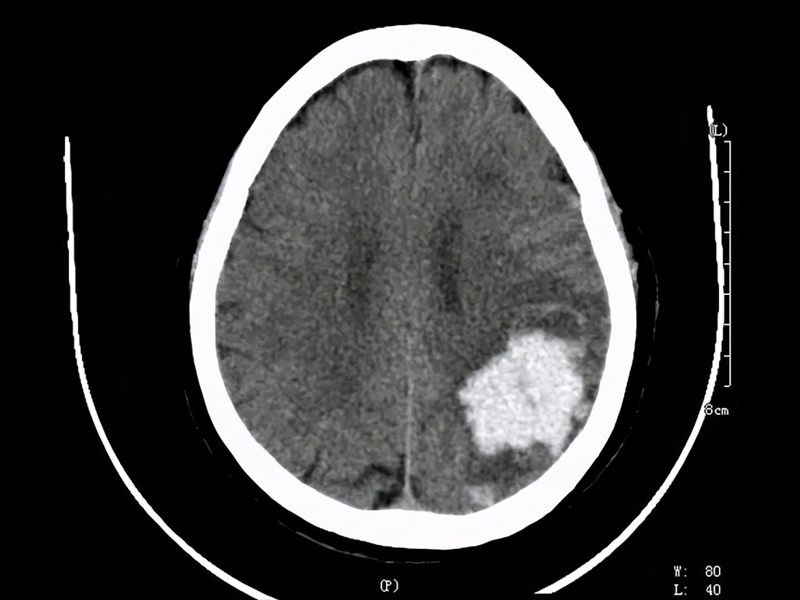

腦幹出血是神經系統的重症,疾病死亡率高。腦幹出血量在 15ml 以下,死亡率約 17.1% 左右;出血量高於 15ml 以上,死亡率 81.8% 左右;若超過20ml死亡率更高。

高血壓動脈硬化是腦幹出血的主要病因,腦幹出血是因高血壓導致基底動脈中央之破裂引起。在數秒到數分鐘內患者就會昏迷、四肢癱、針尖般瞳孔,數小時內會死亡。

1. 腦出血:實質腦內的血管破裂出血。

2. 丘腦出血:破入腦室後容易發生梗塞性腦積水。

3. 橋腦出血:約佔腦出血的10%,多因基底動脈的腦橋支破裂導致。

4. 小腦出血:只實質小腦內的出血,與高血壓直接相關。